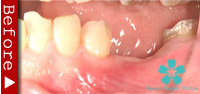

歯のない部分が広い場合

臼歯が失われた場合、従来は取り外し式の部分入れ歯で咬合機能を回復させてきました。

これに対し、インプラントなら天然歯と同様の感覚の”固定式”人工歯を入れることができます。